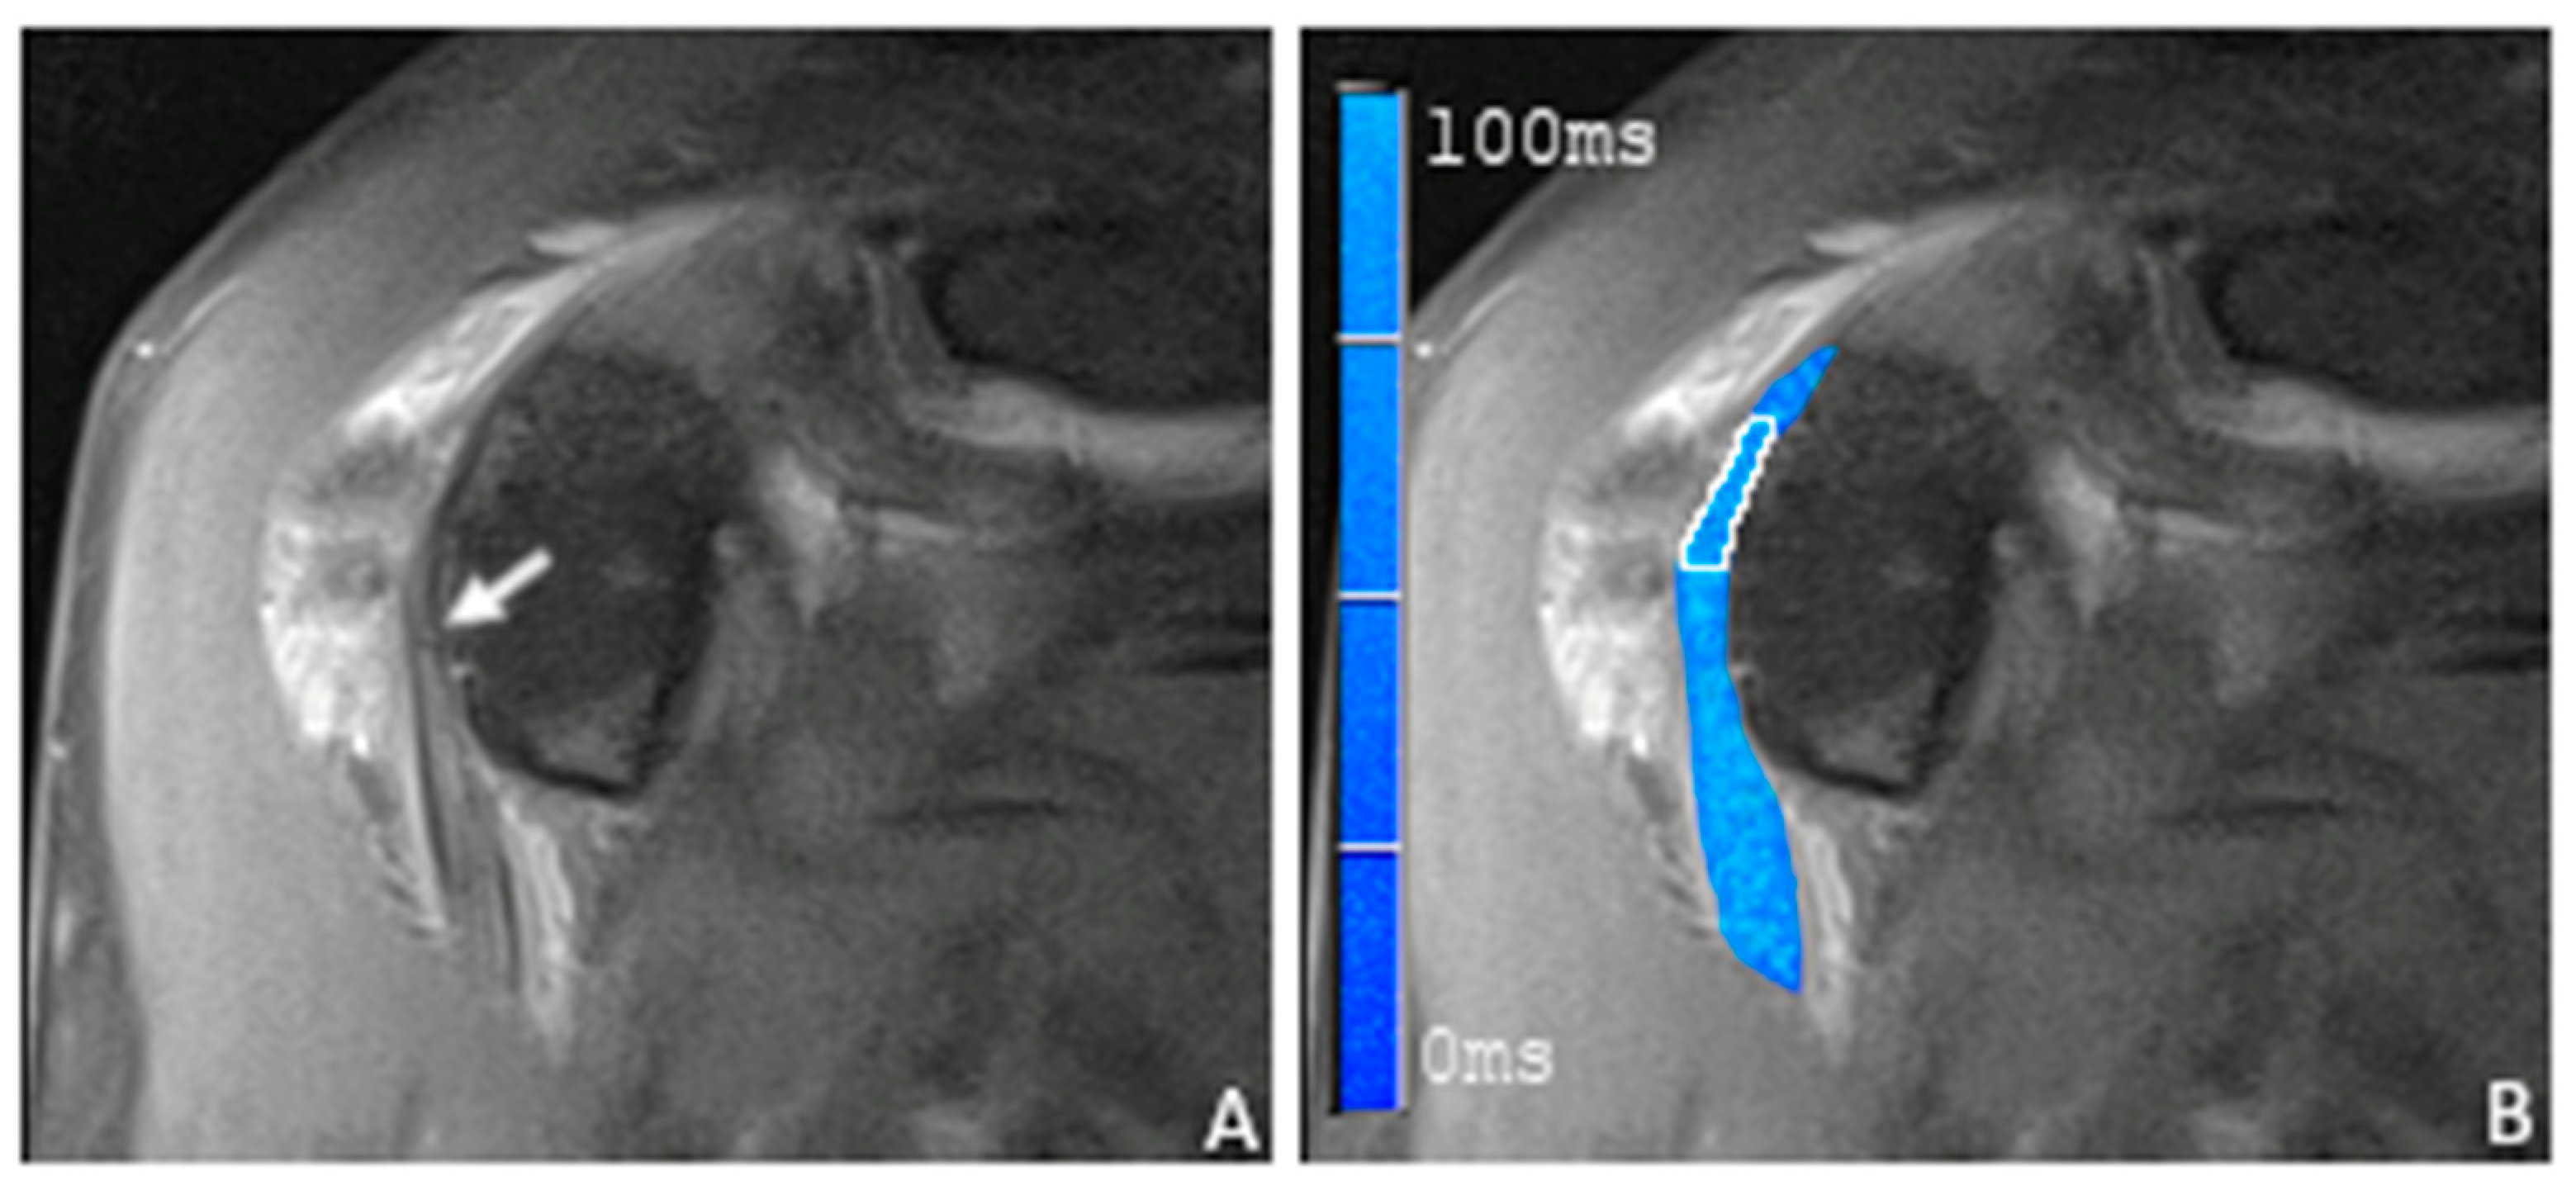

3.2. T2 Mapping of the Long Biceps Tendon

| Overall | Population without Lesion | Population with Lesion | p-Value (t Value) | ||

|---|---|---|---|---|---|

| n | 18 | 10 | 8 | ||

| T2 values (ms) | Mean | 34.2 | 23.3 | 47.9 | <0.001 (−8.33) |

| SD | 13.97 | 4.61 | 7.84 | ||

| Median | 29.0 | 24.2 | 48.2 | ||

| Min | 15.8 | 15.8 | 33.8 | ||

| Max | 61.4 | 29.6 | 61.4 | ||